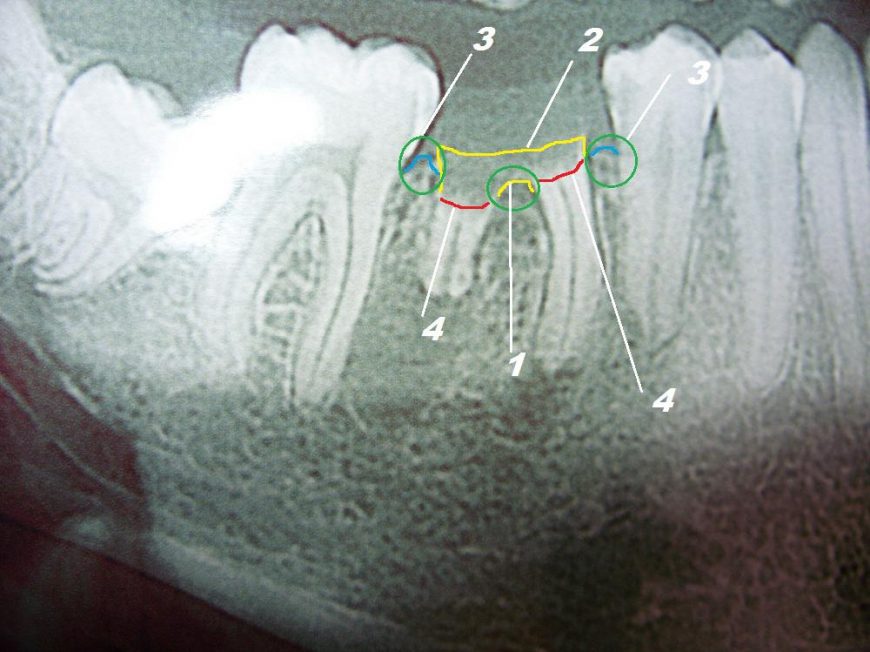

Анатомия: Межкорневая костная перегородка

Раздел: Галерея впечатлений